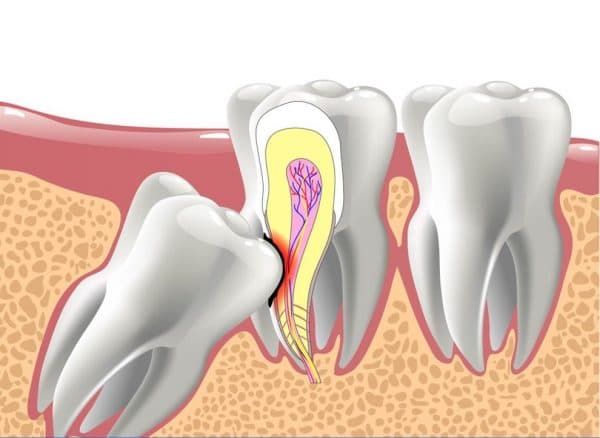

Răng khôn mọc lệch hoặc mọc ngầm có thể gây ra nhiều vấn đề nguy hiểm. Trường hợp răng khôn kẹt trong xương hàm hoặc nướu răng, trong quá trình mọc răng sẽ gây áp lực lên vùng xương và nướu, cùng với việc thức ăn đọng bên dưới nướu phủ trên răng khôn không thể làm sạch được dẫn đến viêm nhiễm.

Răng khôn mọc lệch, không chỉ dễ gây mắc thức ăn tạo điều kiện cho vi khuẩn phát triển mà còn có thể tác động lên răng bên cạnh gây xô lệch hàm, áp lực mọc răng khôn cũng có thể gây ra tiêu ngót chân răng của răng bên cạnh. Bên cạnh đó, răng khôn có thể thoái hóa thành u, nang bệnh lý trong xương hàm, làm yếu xương hàm.